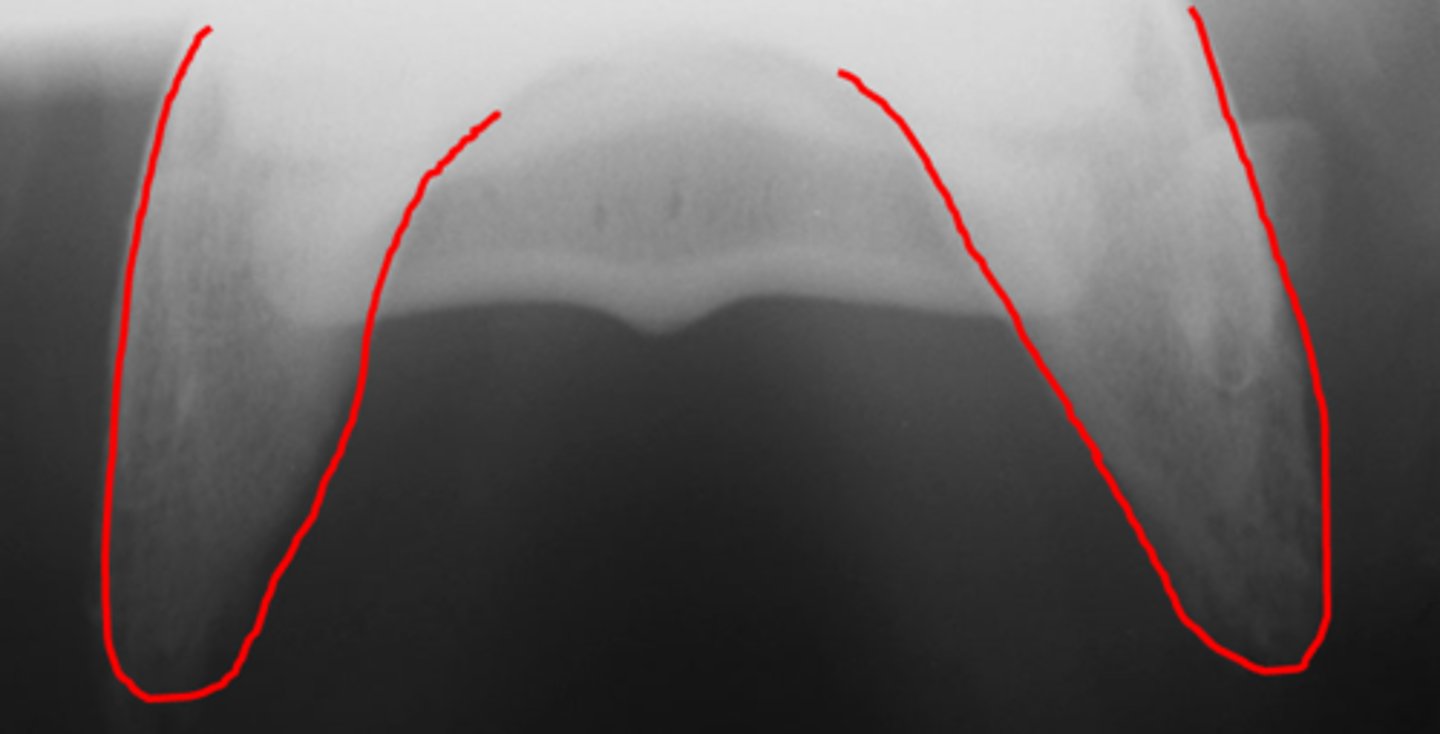

Pastern joint, LM

ID joint and view

Pastern joint, DP

ID joint and view

Short pastern (P2)

Long pastern (P1)

Pastern joint (proximal interphalangeal joint)

Distal sesamoidean ligament

Long pastern (P1)

Short pastern (P2)

Medullary cavity

Nutrient foramen of P2